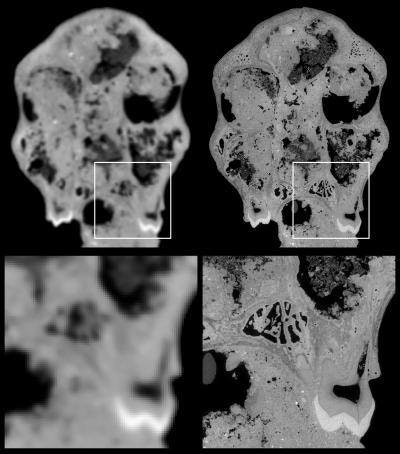

Paleontologists have frequently used medical imaging modalities such as CT to gain insight into archeological specimens without harming them. But South African researchers had to resort to an even more powerful technology -- synchrotron microtomography -- after medical CT failed to provide the required level of detail. In the process, they've discovered key findings about the brain composition of Australopithecus sediba that may bring about changes in evolutionary theories.

By examining the inner surface of the skull, the researchers hoped to recreate the shape and size of the brain. While the skull of the juvenile was originally examined with a medical CT scanner, the data did not allow detailed investigation of the internal structures, according to Carlson and colleagues.

The radiation produced from the beam is captured by straight beamlines that branch off of the ring. Fossils or other objects can be placed at the ends of these beamlines for imaging. Using a beamline at the ESRF, the group was able to scan the skull at a resolution (3D pixel size) of approximately 45 microns.

"Imaging a partial hominum cranium filled with matrix and still achieving a resolution exceeding 100 µm (i.e., voxel size smaller than 50 µm) with phase contrast presented a considerable challenge," Carlson and colleagues wrote. Previously, synchrotron imaging had generally been limited to smaller fossils.

One difficulty is that the larger size of the stone-filled cranium (approximately 15 cm) resulted in too low of a transmission level, or the ratio between the direct beam and the beam after passing through the sample, according to the authors. Even with the strongest energy level available (150 keV), with a direct beam at the limit of the camera's saturation, high-quality images could not be obtained.

To address this, they used a protocol that "substantially increases the amount of photons going through the middle of the sample, but without reaching the saturation level of the detector," Carlson and colleagues wrote. By adding a configuration of aluminum in front of the beam, as well as placing the cranium within a specially designed Plexiglas cylinder filled with aluminum or glass balls, they were able to effectively "normalize" x-ray absorption across the entire field-of-view.